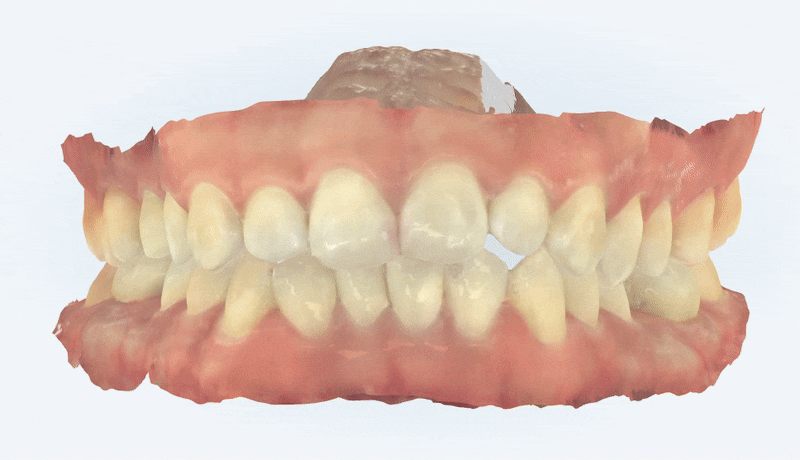

이 환자분께서는 비발치 세라믹 교정으로 진행하셨습니다.

세라믹 교정을 통해

치아 크기에 비해 악궁이 좁아

삐뚤빼뚤했던 치아들이 제 위치를 찾고

앞니끼리 맞물렸던 이전과 달리

잠실비발치교정을 통해 교합이 바르게 자리 잡았습니다.

위, 아래 앞니 안쪽에는

치아가 돌아오는것을 예방하기 위해

유지장치를 붙여 마무리해드렸습니다 ^^

교정 완료 후에는

잇몸라인의 균형을 위해

잇몸레이저를 통해 거미스마일을 개선해드렸습니다.

교정완료 후엔 전문가치아미백치료로

치아들이 한층 더 밝아진 모습입니다.

우측: 교정 완료 후 Smile Arc 가 잘 형성됨.